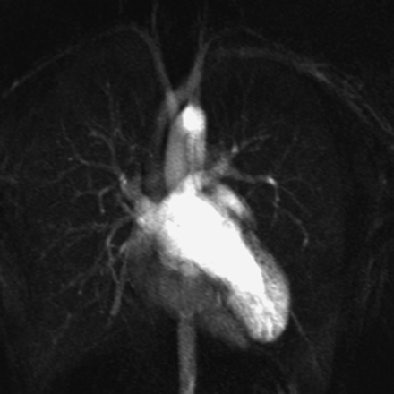

| Fig. A (above), 23-year-old woman referred to MRI with suspicion of transposition of great arteries because of prominent trabeculation of subaortic ventricle in echocardiography. Time-resolved coronal maximum-intensity-projection angiograms (B-C, below) and cine short-axis view (D, bottom). The angiograms show normal time course of enhancement of subpulmonary atrium and ventricle and pulmonary arteries (A); and enhancement of pulmonary veins, subaortic atrium, ventricle, and aorta (B). Note decreasing enhancement of subpulmonary ventricle from A to C, indicating absence of relevant left-to-right shunt flow. This patient suffered from noncompaction myocardium, which is visualized on time-resolved MR angiography (C) (arrow) and is shown on cine short-axis view (D) (arrows). Republished with permission of the American Roentgen Ray Society from AJR 2006; 187:1107-1114. |